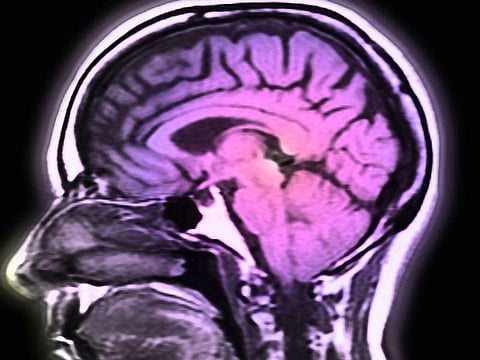

First, BRAVO1 underwent surgery to implant an "array" containing 128 tiny electrodes onto the surface of his speech motor cortex — the part of the brain that's active when we speak. After recovering, BRAVO1 attended 48 sessions, over several months, where the electrodes recorded his brain activity as he attempted to say each of 50 vocabulary words — over and over.